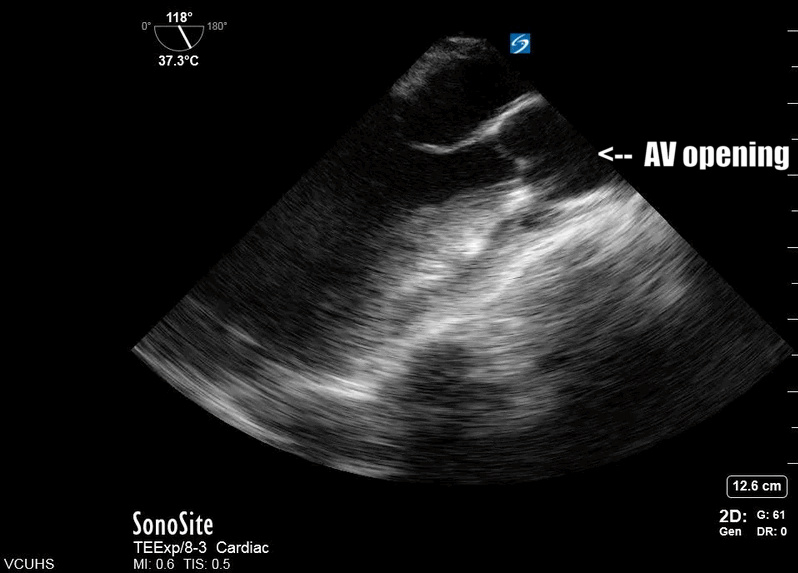

The TEE mid-esophageal long axis view (ME-LAX) is the mirror image of the parasternal long axis view in transthoracic echo (TTE), with the left atrium closest to the probe face and the right ventricle (RV) furthest from the probe. To achieve this view, the TEE probe is inserted approximately 30-35cm until a mid-esophageal four chamber view is obtained. From this starting point, the omniplane is rotated to 120 degrees, then further fine adjustments are made to the omniplane and probe rotation until a view showing both mitral inflow and aortic outflow to the left ventricle (LV) is achieved (Fig. 1). This view is excellent for evaluating LV contractility and assessing aortic and mitral valve function.1 During resuscitation, this view is key to real-time evaluation of CPR effectiveness.

Figure 1. TEE ME-LAX view showing severely reduced ejection fraction (EF) following ROSC

Most importantly for the resuscitationist, the ME-LAX view is used to evaluate the quality of CPR and hand placement for chest compressions; so it should be obtained during initiation of CPR and even when changing CPR providers if possible. Optimal chest compressions should result in vigorous LV squeeze with near concurrent aortic valve opening (Figure 2). Incorrect compressions, usually too high on the chest wall, will result in LV outflow obstruction and ineffective CPR (Figure 3). This can be seen on the ME-LAX view as squeeze over the AV itself, narrowing of the aortic outflow tract, absence of LV compression and/or absence of aortic valve opening during compressions. Signs of ineffective CPR should prompt adjustments in compression location and/or depth and subsequent re-evaluation for effectiveness.2

Figure 2. Me-LAX view during CPR (slowed to 50% speed) showing mid-LV compression with concurrent aortic valve opening